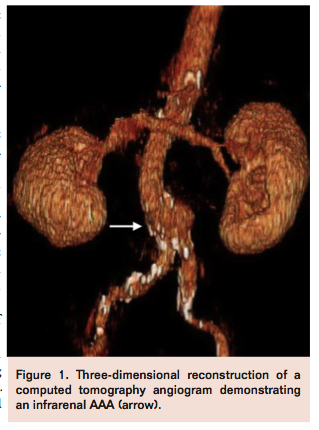

A 62-year-old male with a known history of abdominal aortic aneurysm (AAA), coronary artery disease with ischemic cardiomyopathy, hypertension, and dyslipidemia presented to the endovascular clinic for a 6-month follow-up of his AAA. Physical examination was remarkable for a palpable abdominal mass and a soft bruit. Vascular exam was within normal limits with 2+ pulses bilaterally in the femoral, popliteal, and pedal segments. Computed tomography (CT) angiography of the abdomen and pelvis measured the AAA at 5.5 cm in oblique AP diameter (Figure 1) compared to 5.2 cm at preceding study 6 months prior. The iliac and femoral arteries were noted to be large and relatively free of disease. In the setting of a progressively enlarging AAA, a decision was made to perform an endovascular aneurysm repair (EVAR) of the AAA.